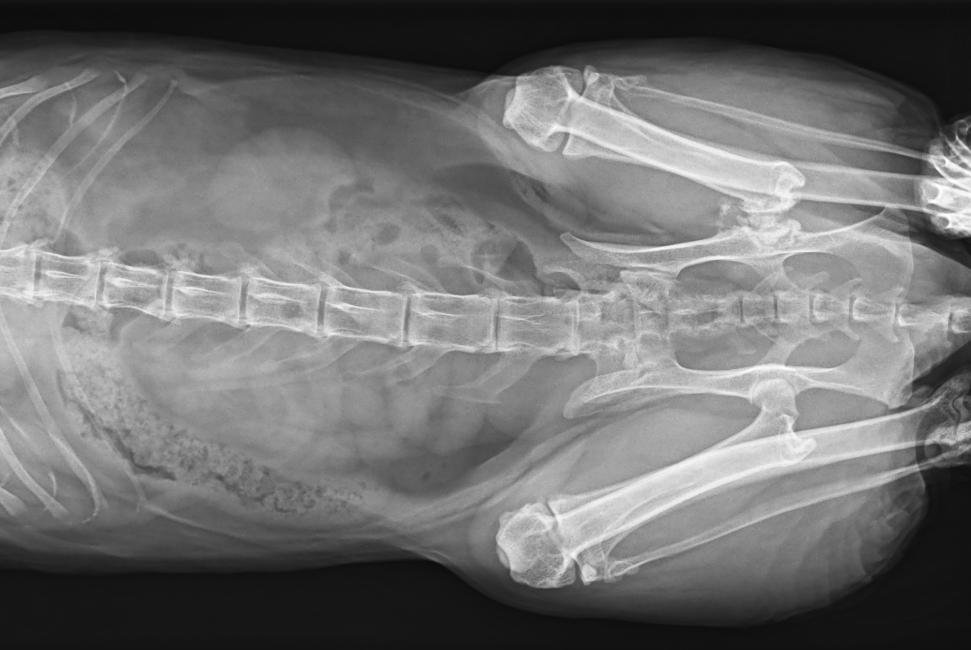

● 可浮動床面設(shè)計,滿足大部分中小型寵物檢查

● 靈巧機架設(shè)計,近臺操作,手動/遙控曝光,結(jié)構(gòu)靈活緊湊

● 占地面積小,滿足多種安裝條件